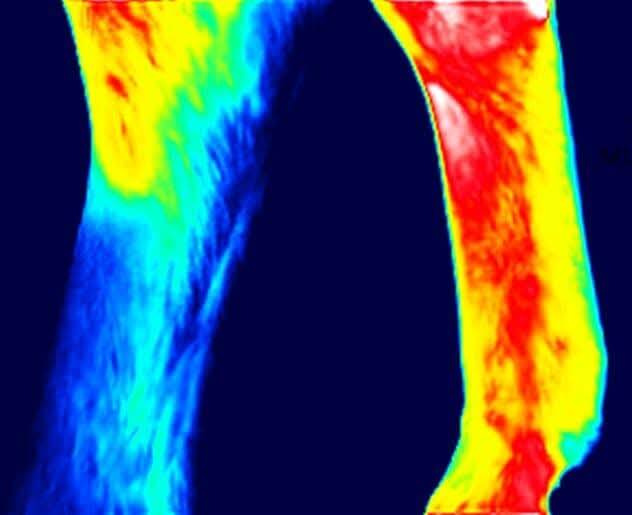

Mithilfe einer speziellen Infrarotkamera wird die Oberflächentemperatur des Pferdekörpers gemessen und bildlich dargestellt. Temperaturveränderungen können auf Entzündungen, Durchblutungsstörungen oder muskuläre Verspannungen hinweisen. Besonders in der präventiven Tiermedizin sowie zur Unterstützung bei Diagnosen und Therapieverläufen ist die Thermographie ein wertvolles Werkzeug.

Die unten aufgeführten Bilder sollen nur einen kleinen Einblick in die Möglichkeiten der Lokalisierung von Beschwerden gewähren und zeigen, wie sich diese darstellen.